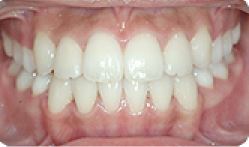

| 9 |

|

임플란트 전후사례 | 2020.03.06 |